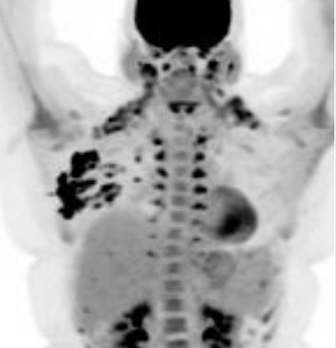

Lactating Adenoma

Lactating adenomas are benign (non-cancerous) masses comprised of dense glandular tissue and most commonly occur in the upper outer part of the breast. They can present during pregnancy or lactation and likely are related to hormonal stimulation. They may become large; however, they reduce in size as a woman progresses further in the postpartum period and eventually disappear when lactation is complete. They can appear similar to fibroadenoma on breast imaging, as smooth, oval lesions. Diagnosis can be confirmed with a core needle biopsy, but they do not require surgical excision.